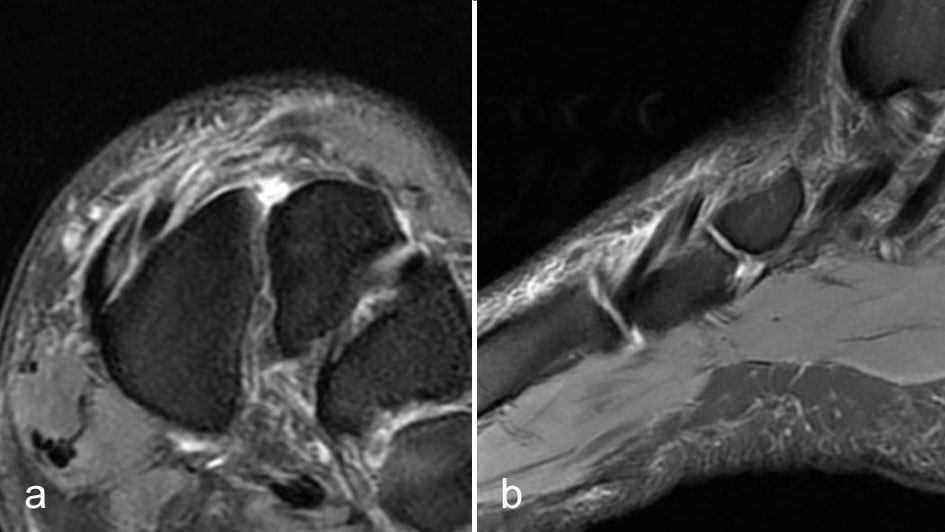

Die Gelenkkapseln der Metatarsophalangealgelenke und Interphalangealgelenke haben plantar eine kräftige faserknorpelige Verstärkung. Sie wird als plantare Platte bezeichnet. Die plantaren Platten sind über die seitlich einstrahlenden Ligg. metatarsale transversum profundum miteinander verbunden. Beugeseitig ist die Sehnenscheide der Flexorensehnen mit der plantaren Platte verwachsen. Degeneration und Rupturen führen zu einer Überstreckbarkeit dieser Gelenke.

Rupturen ereignen sich am häufigsten an den distalen Insertionen der Metatarsophalan­gealgelenke (Abb. 5), etwas seltener auf Höhe der Metatarsaleköpfchen. Die Läsionen können sehr umschrieben sein, quer durch die gesamte plantare Platte reichen und sich sogar bis in die Kollateralbänder fortsetzen 1. Rupturen der plantaren Platte finden sich am häufigsten an der zweiten Zehe, die dritte Zehe ist etwas seltener betroffen. An der vierten und fünften Zehe sind die Läsionen sehr ungewöhnlich. Rupturen der pantaren Platte führen häufig zu einer ausgeprägten Weichteilreaktion, die nicht als Morton-Neurom fehlgedeutet werden sollte (Abb. 6) und zur Ausbildung einer Neo-Bursa führen können (Abb. 7).